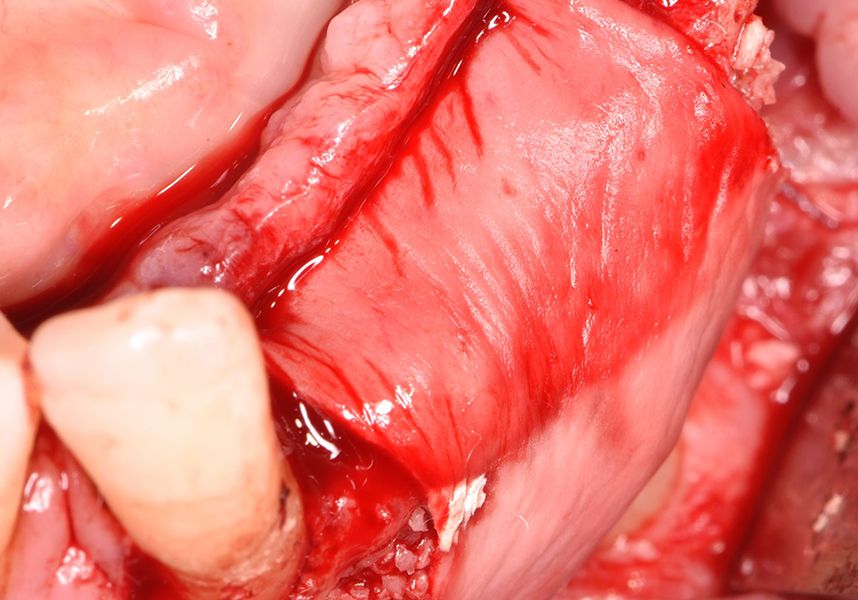

Respecting the three-dimensionally correct position of the implant led to bone fenestration, leaving the apical part of the apex of the implant exposed almost to the mid-point of its length at 42 and a third in 32.

To treat the defect, bone regeneration was carried out simultaneous to the surgical process, with an autologous bone graft from the patient. In the internal part of the graft we used autologous cortical bone obtained by scraping (Safescraper) and from the biological drilling, at low revolutions and without irrigation, from the other implant beds. In the external layer of the regeneration we used a xenograft (Genoss, Osteogenos) and this was covered with a reabsorbable collagen barrier membrane (Evolution STD, Osteogenos).